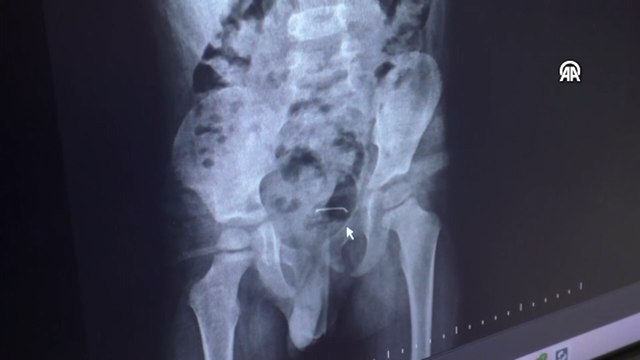

KAHRAMANMARAŞ'ta yaşayan Ramazan Orçan, arkadaşının doğum günü için gittiği pastanede yediği pastadaki iğnenin boğazına saplanması sonucu hastanelik olduğunu öne sürdü. Orçan, iğnenin ameliyatla çıkarıldığını ve taburcu olduktan sonra pastane yetkilileri hakkında suç duyurusunda bulunacağını söyledi.